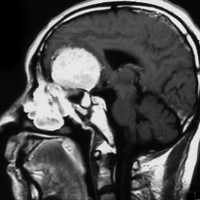

大後頭孔(大孔)髄膜腫 foramen magnum meningioma)

この腫瘍はfarlateral approachなどの頭蓋底手術をしなくても,外側後頭窩開頭で全摘出できます。要領は,S状静脈洞の下端の周囲骨を削除することです。大後頭孔髄膜種は延髄を圧迫するので巨大なものはありません。出血のコントロールや延髄からの剥離は比較的容易なものが多いでしょう。舌咽神経と迷走神経損傷を避けることが重点となります。

迷走神経と舌咽神経は機能温存できました。舌下神経が腫瘍の表面に薄く広がり剥がすことができずに半分以上を切断しています。でも片側舌下神経麻痺では日常生活に困ることはあまりありません。